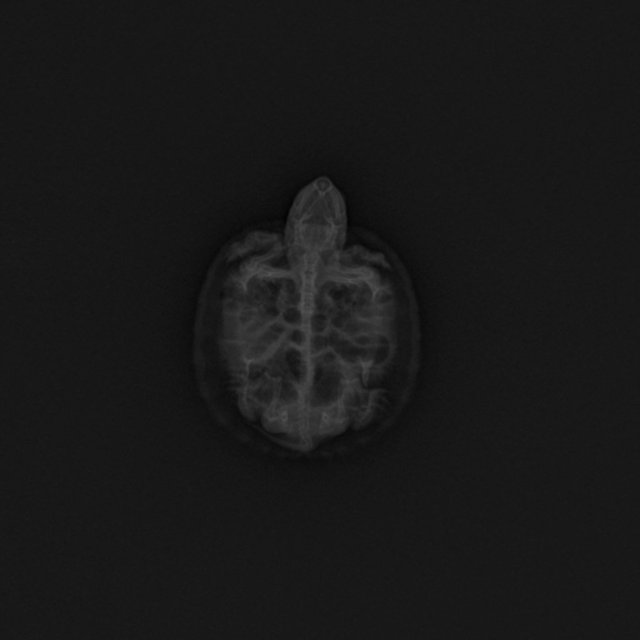

Итог по рентгену: врожденная патология внутренних органов. В настоящий момент там пустота (его слова). Уточнила,что это значит. Сказал, что органы усохли, атрофировались, и что это не итог какого-то неправильного содержания, а врожденная аномалия. Также мягкий панцирь, рахит. Она похудела ещё больше,т.к. не ест уже больше недели и до этого ела крохи.  Есть ли смысл что-то делать, подскажите? Одно фото прилагаю. Фото сбоку не стала забирать, если есть смысл, выкуплю, оно стоит 500 р. Там под панцирем видна пустота. По состоянию почти такая, как в последние дни, но только больше как бы зависает в воде. С островка на островок переплывает.

у черепахи жкт раздут газами, это стандартная проблема черепах на гаммарусе и да, к сожалению они от этого умирают, лечить это сложно. Но тут нет никакой мифической генетической мутации и прочего бреда.

У неё сильные газы в жкт, буквально всё раздуто и пережимает лёгкие и другие внутренние органы. Если получится сейчас заставить жкт работать - ей будет легче.